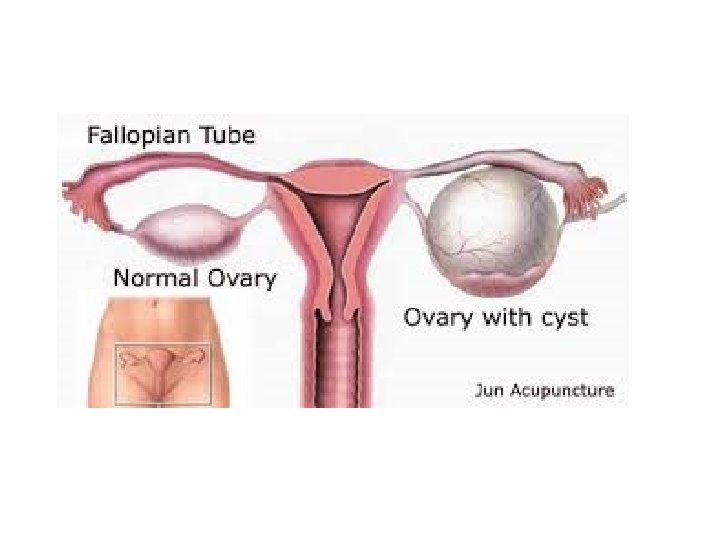

• DIAGNOZA DIFERENCIALE: - Me peritonitin akut nga ruptura te ndryshme si e apendiksit - Barra ekstrauterine - Pankreatit hemoragjik - Torsion ovarial

RUPTURE e shtatezanise ektopike:

• Cdo femer ne moshen e fertilitetit qe paraqitet ne urgjence me dhimbje te abdomenit te poshtem duhet te beje TESTIN E SHTATZANISE!!!!!!!